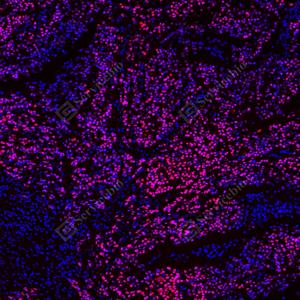

| IF检测p53蛋白(货号 GB151740)(红色). 样品: 人食管癌, 4%多聚甲醛 (货号G1101) 固定12-24小时. 抗原修复: Tris-EDTA抗原修复液(pH 9.0) (G1203), 100℃, 25分钟. 封闭: 3% BSA(货号GC305010)的PBS溶液, 室温孵育30分钟. —抗: 1: 1500稀释, 4℃ 孵育过夜. 二抗: Cy3标记山羊抗小鼠IgG (H+L) (货号GB21301), 1: 300稀释, 室温孵育1小时. |